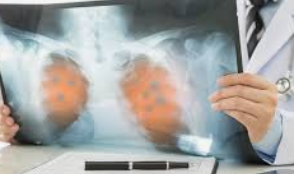

- 흉부 X-선 검사: 폐 내부의 결핵 병변을 확인하는 데 사용됩니다.

- 흉부 CT 검사: 필요시, 보다 정밀한 검사를 위해 시행됩니다.

- 정기적인 검사: 치료 중에는 정기적으로 객담 검사와 흉부 X-선 검사를 통해 치료 효과를 모니터링합니다.